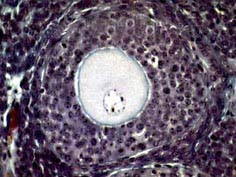

如图,可将卵泡的生长过程分为以下几个阶段 ( ) 1NS-02441.jpg 1NS-02442.jpg 1NS-02443.jpg 1NS-02444.jpg

• A.排卵前卵泡

• B.始基卵泡

• C.卵泡闭锁

• D.窦状卵泡

• E.窦前卵泡